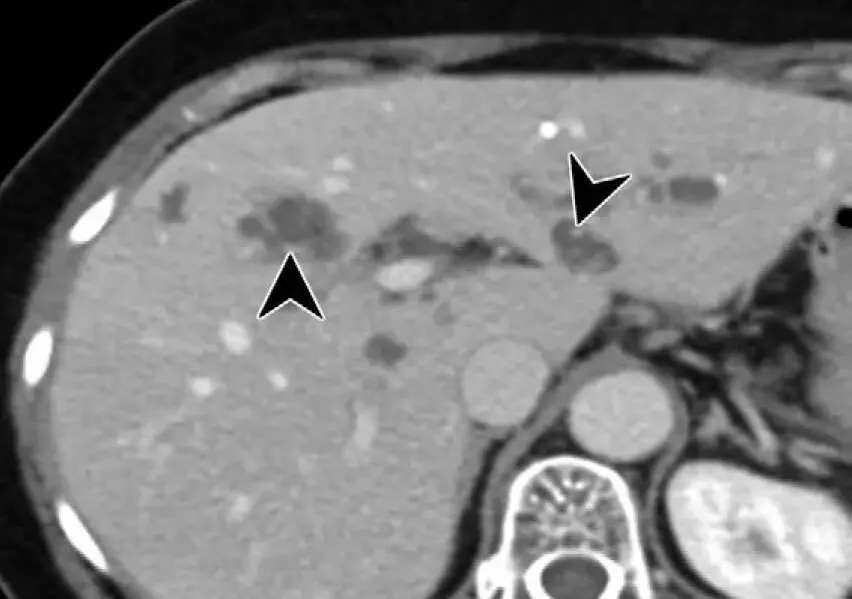

行CT检查提示,胆总管结石伴肝内外胆管扩张;肝内末梢胆管扩张,肝内胆管絮状影,考虑为肝吸虫感染;胆囊结石。

CT检查提示,患者肝内胆管絮状影,考虑为肝吸虫感染